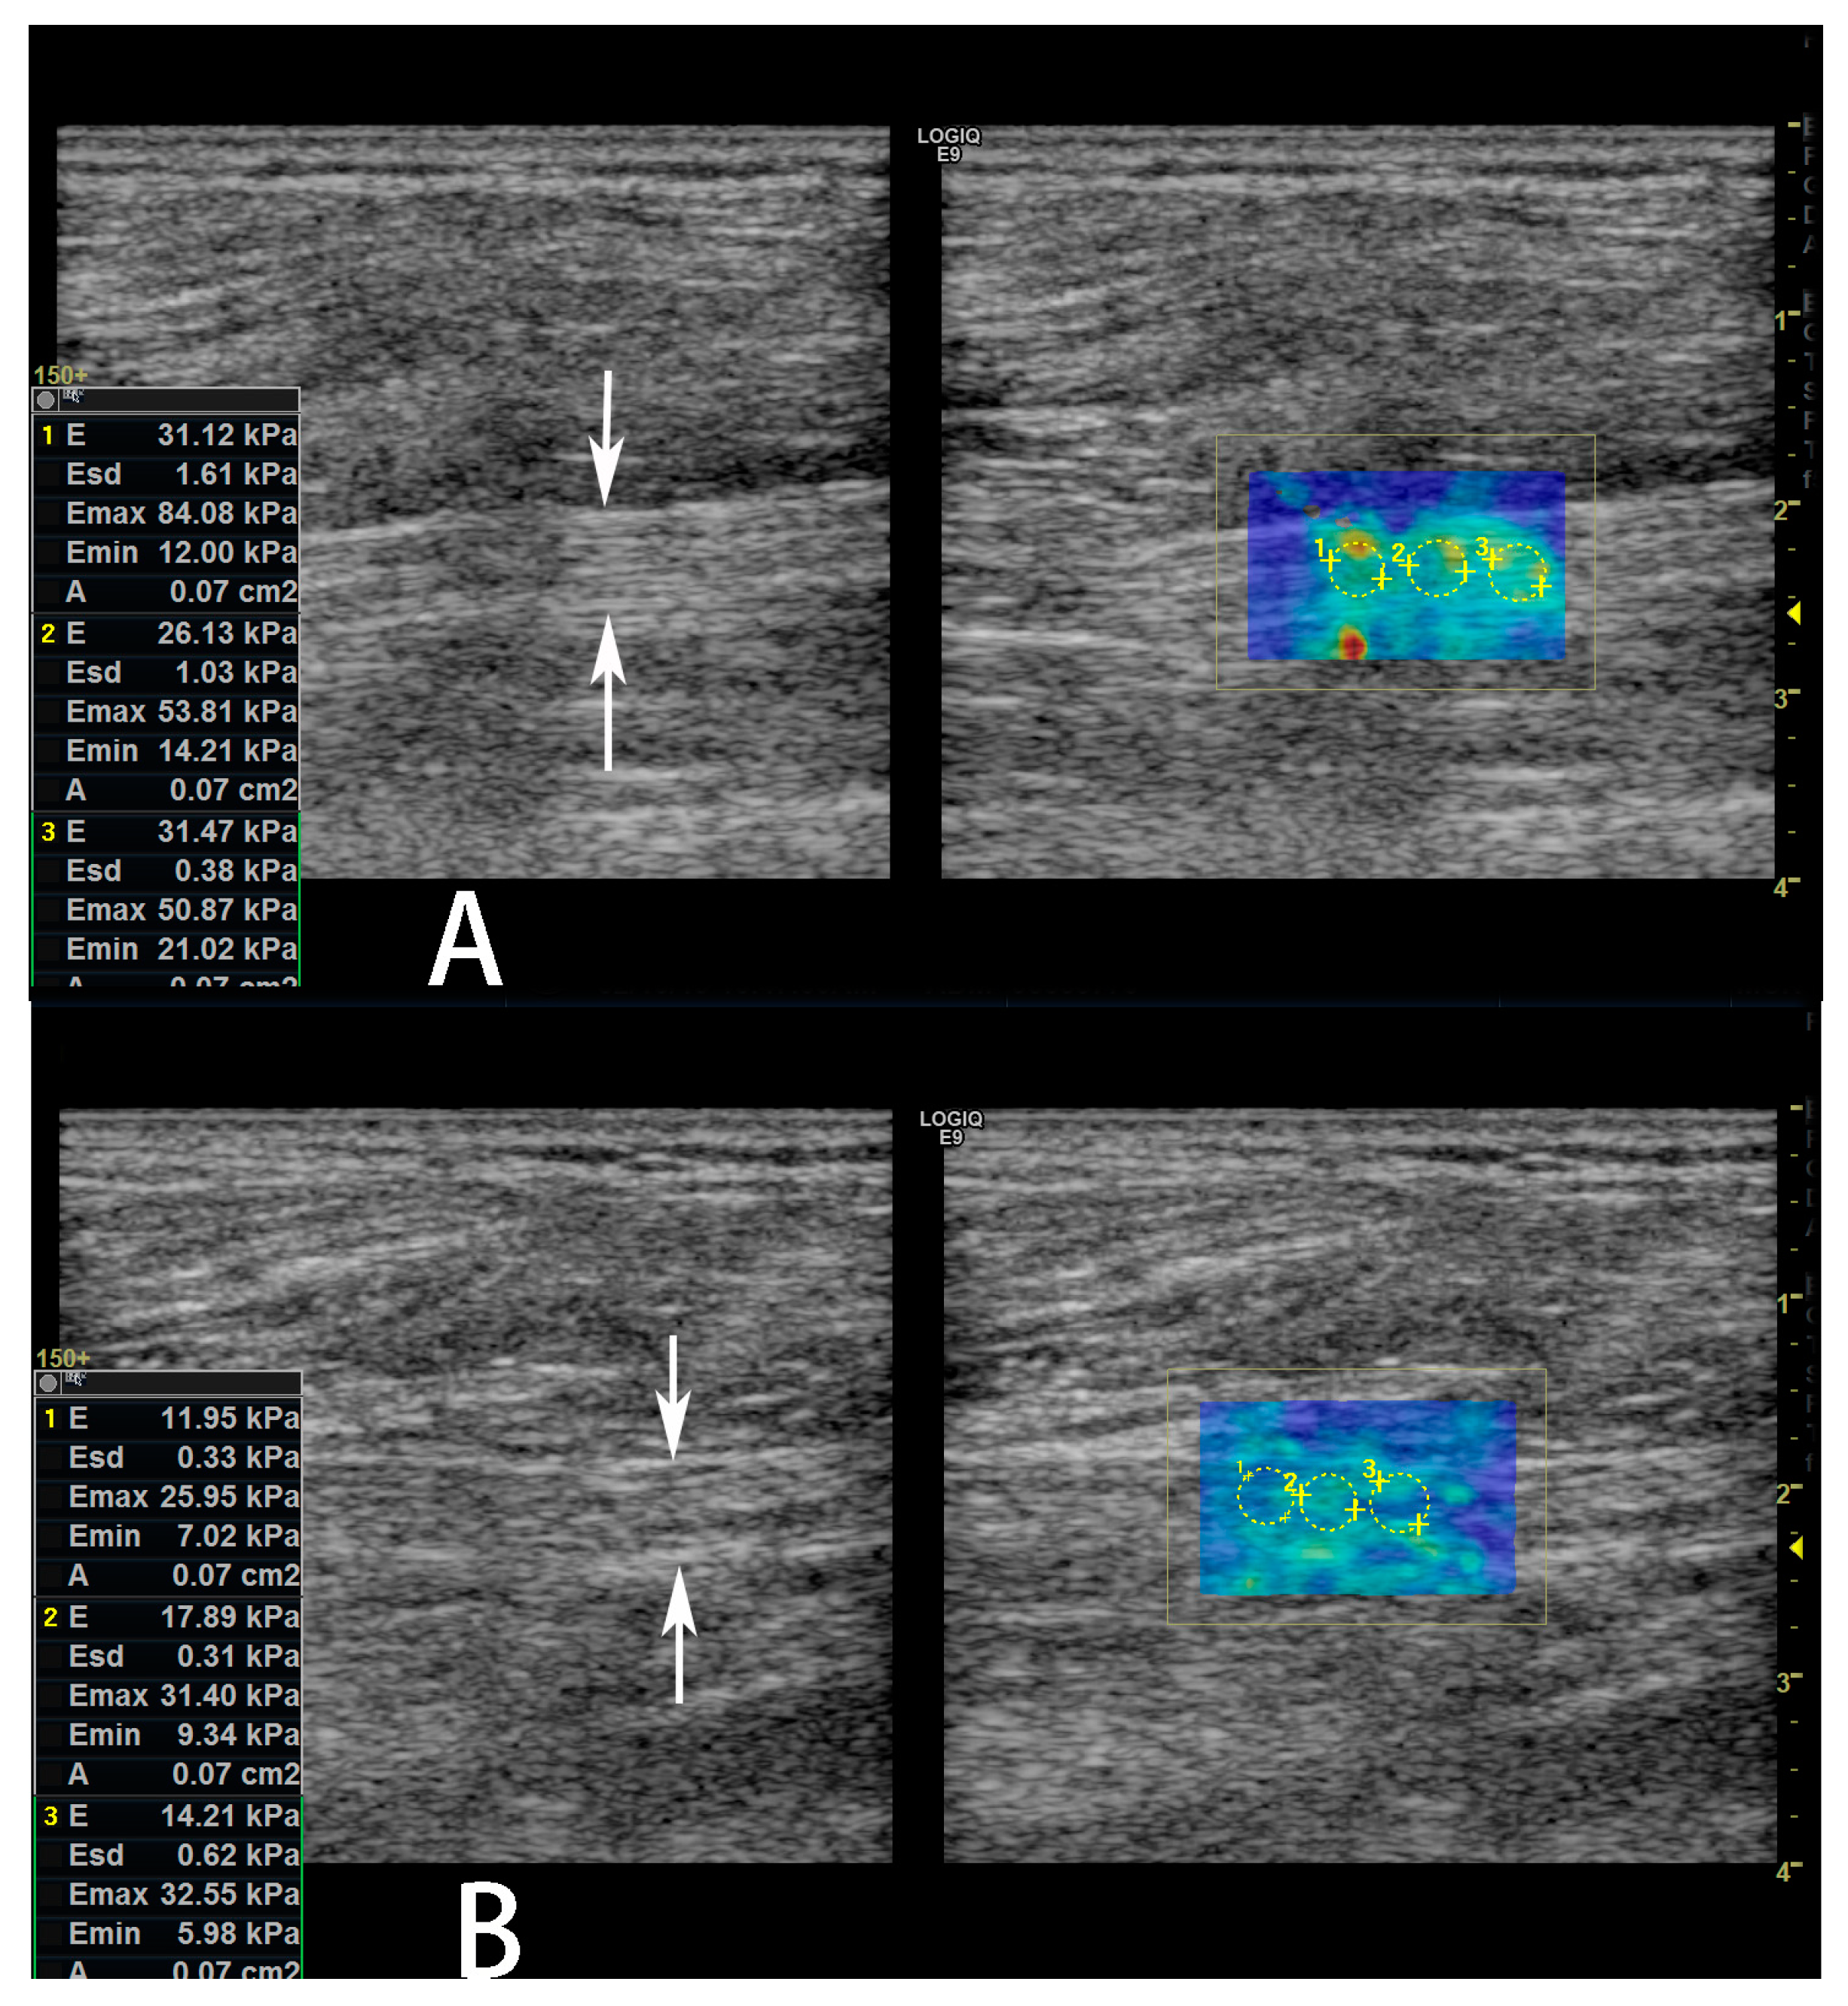

A significant difference (p < 0.05, Table 2 and Figure 3) was found between the elastographic (SWE) stiffness values of the sciatic nerves of the two groups. Namely, SWE stiffness values in the sciatic nerve in the DFU group are higher than the non-DFU group. When the SWE values were used for prediction of DFU in patients with DPN, the area under the ROC curve (AUC) was 0.727 (95% confidence interval [CI]: 0.541–0.868, Figure 4). When we used the best SWE value of 24.48 kPa as a cutoff for prediction of DFU, the sensitivity and specificity were 62.50% (95% CI: 35.4–84.8%), and 75% (95% CI: 47.6–92.7%), respectively. When we used the SWE values of 10.45 kPa and 42.8 kPa as cutoff for prediction of DFU, the sensitivities were 100% (95% CI: 79.4–100.0%) and 12.50% (95% CI: 1.6–38.3%), respectively, while the specificities were 31.25% (95% CI:11.0–58.7%) and 100.0% (95% CI: 79.4–100.0%), respectively. However, there was no significant correlation between the SWE stiffness values of the sciatic nerves in the lower limbs with DFU and Wagner’s grade for the ulcers (r = 0.151, p = 0.576).

Figure 3.

Shear wave elastography (SWE) images of the sciatic nerve in a 61-year-old male diabetic patient with diabetic peripheral neuropathy (DPN). He also had a diabetic foot ulcer (DFU) on the left lower limb. The average SWE stiffness value of the left sciatic nerve was 29.57 kPa (A), which was higher than SWE stiffness value of the sciatic nerve, average 14.68 kPa; (B) the right lower limb without DFU.